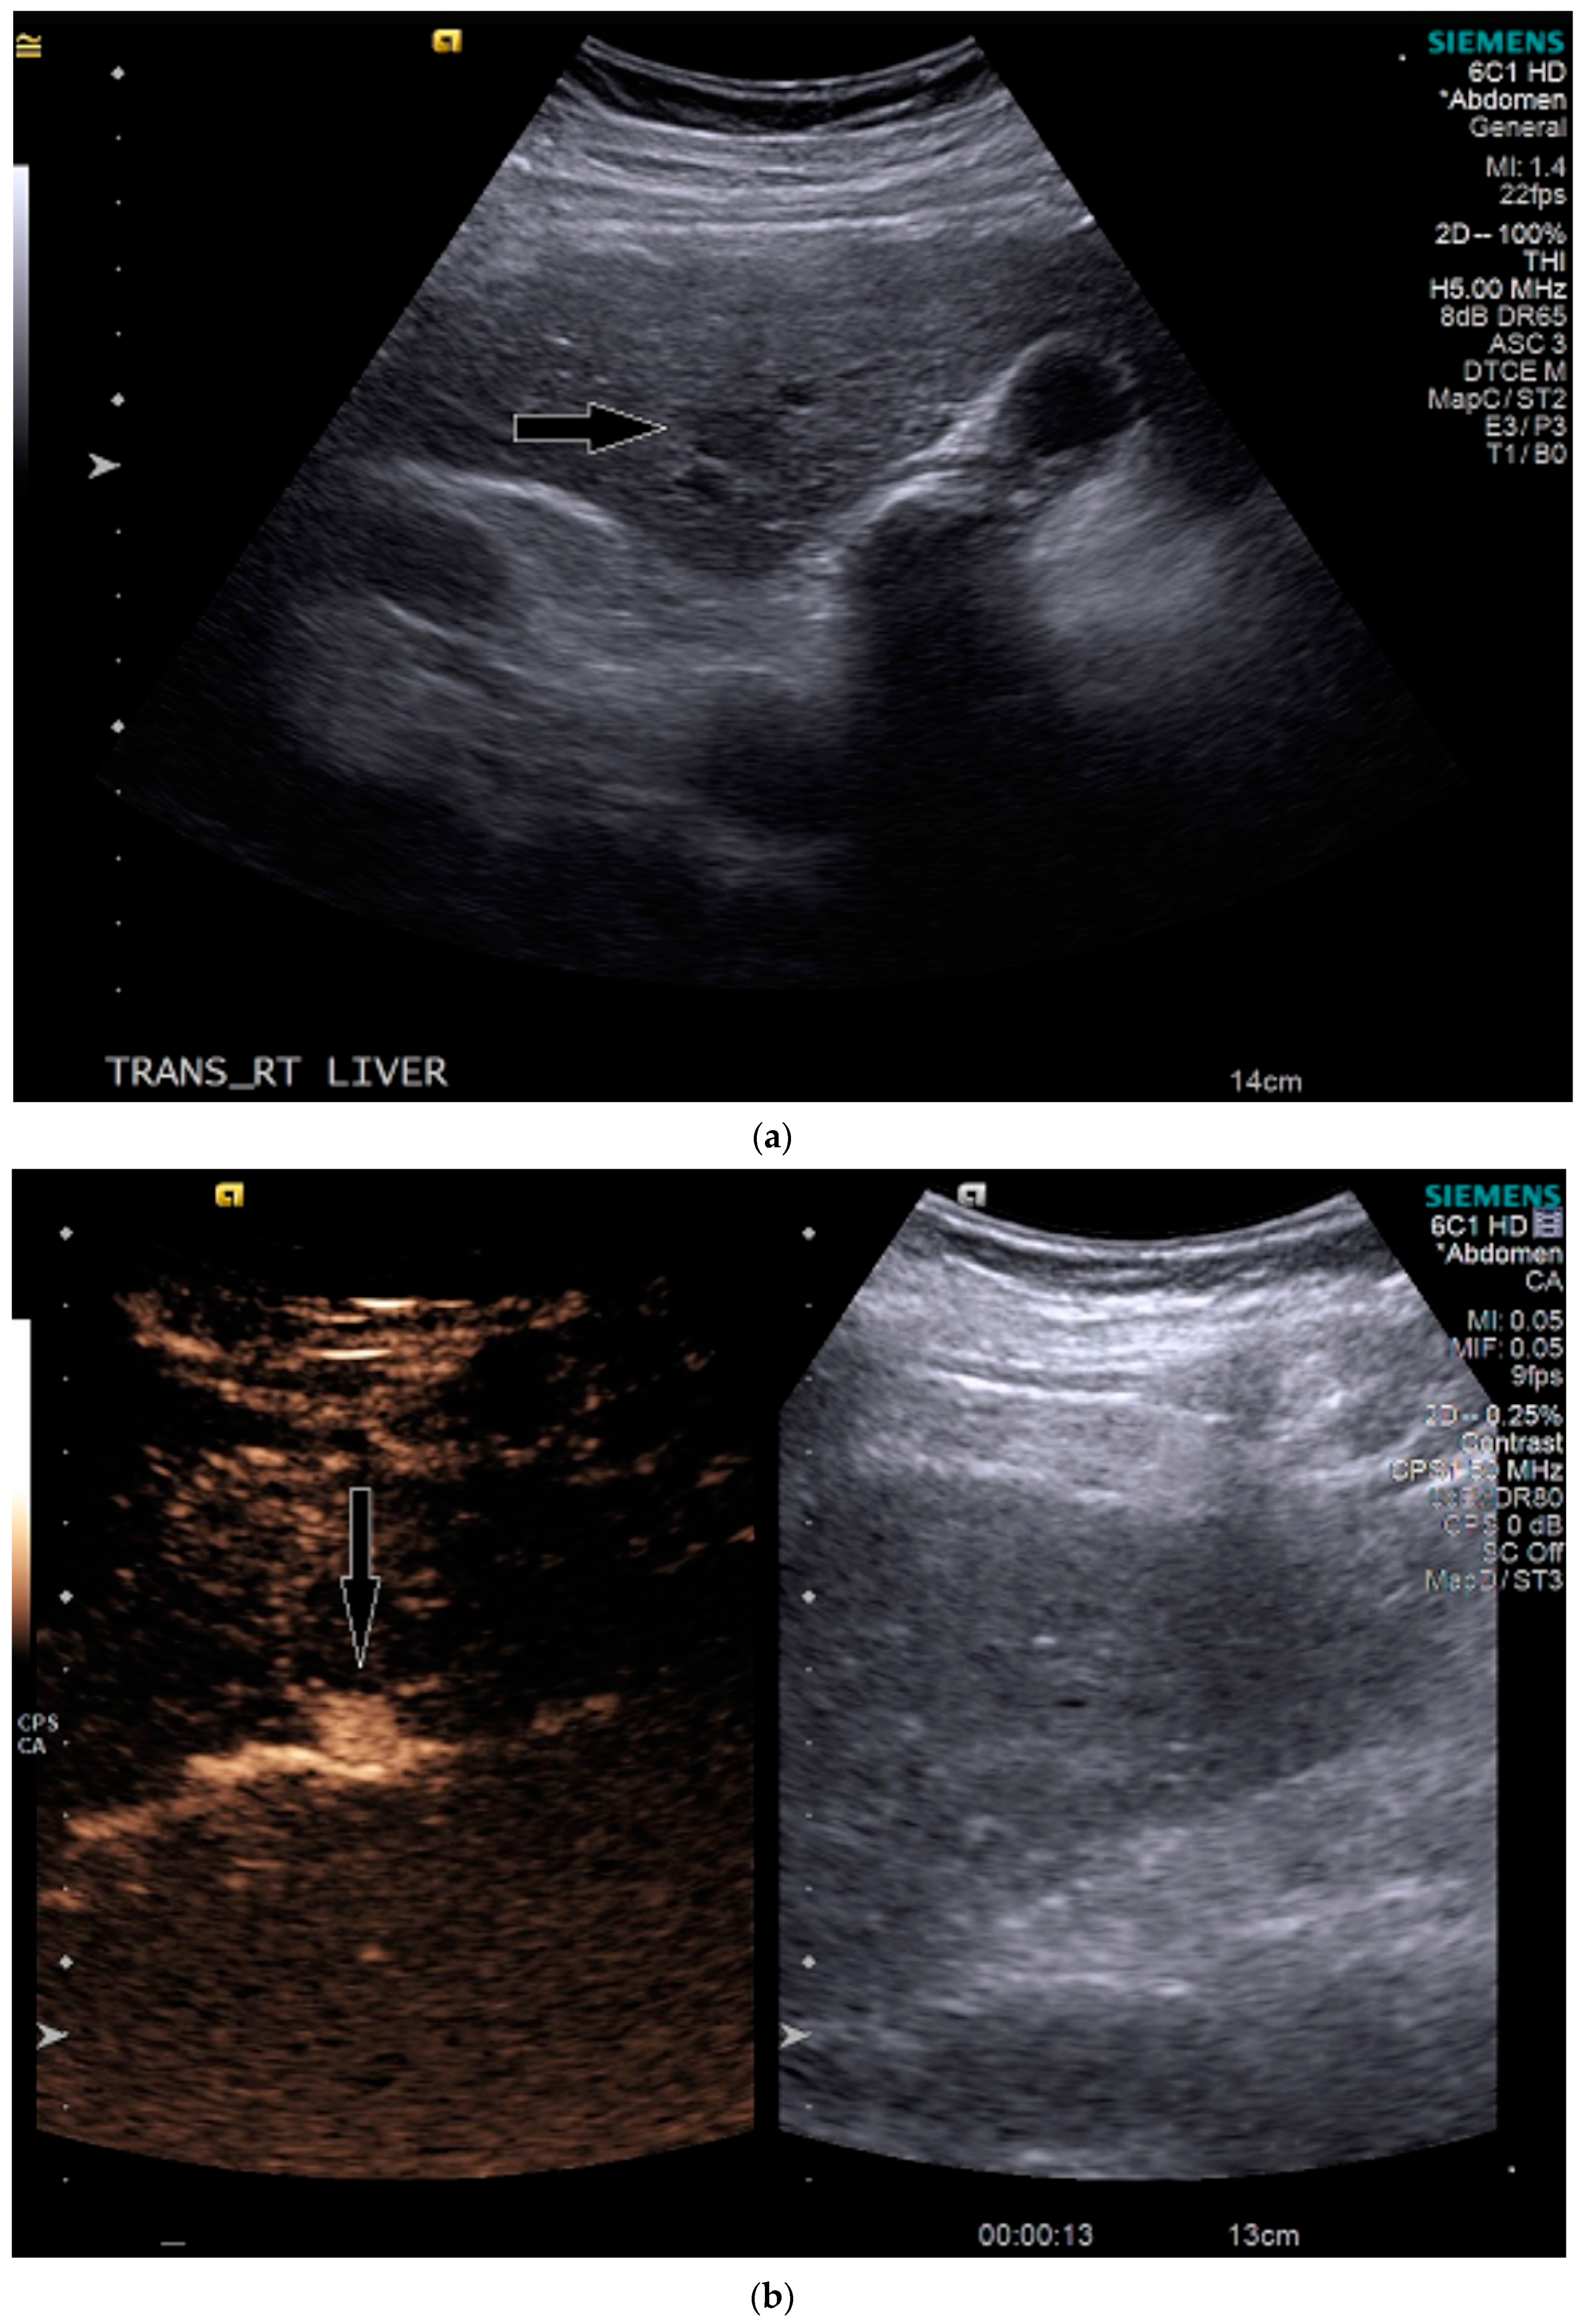

3.1. Case 1

3.2. Case 2

3.3. Case 3